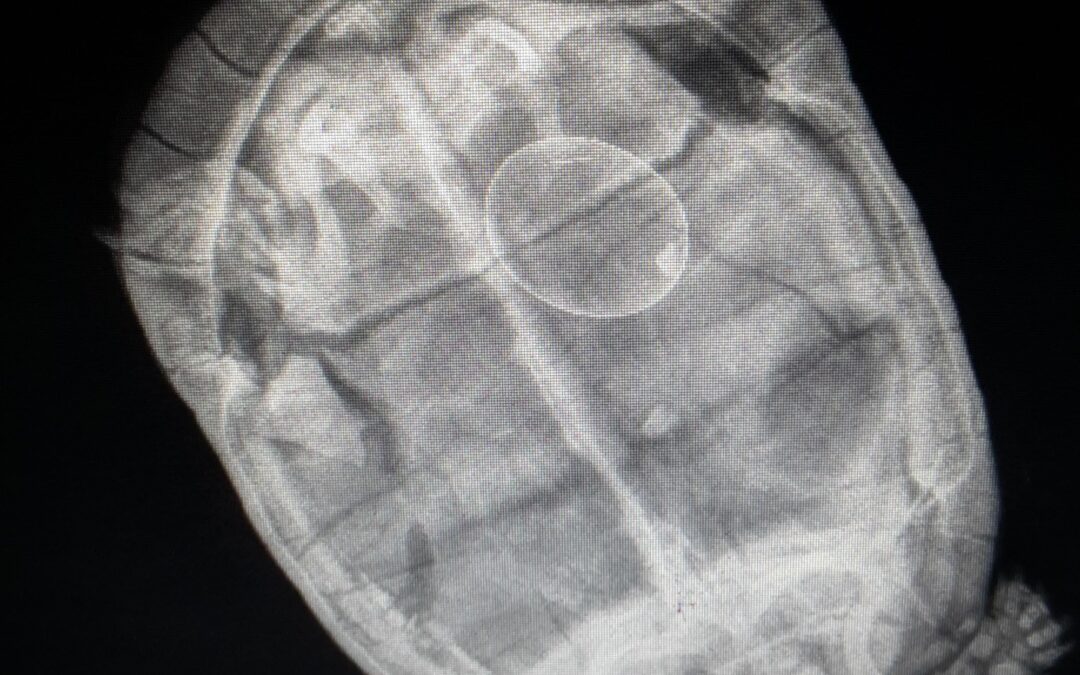

Les examens radiographiques sont effectués au sein de la Clinique Vétérinaire du Mail, ils nécessitent fréquemment une tranquillisation de l’animal afin d’obtenir des images de qualité.Les clichés radiographiques sont remis au propriétaire. Les examens...